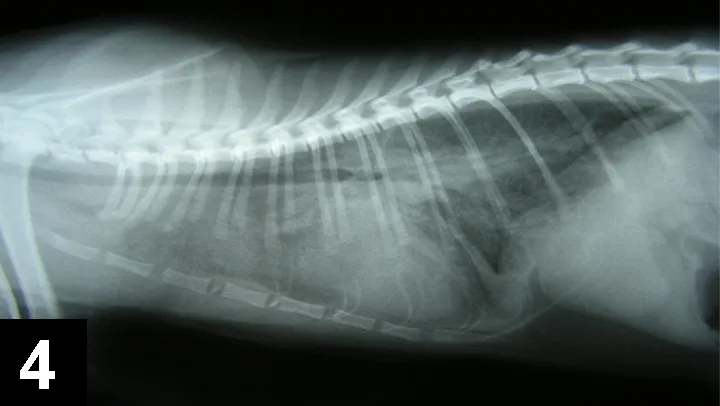

Treatment of ComplicationsClinical signs of overhydration include tachypnea, orthopnea, serous nasal discharge, chemosis, pulmonary crackles, and subcutaneous pitting edema (Figures 3 and 4). In animals with renal insufficiency or failure, careful titration of fluid therapy is essential, as decreased urine output may result in intravascular volume overload.

A lateral radiograph of a canine thorax shows the ribcage, spine, and heart silhouette, with clear delineation of the lungs and diaphragm. The image highlights the anatomical structures for evaluation of respiratory and cardiovascular health.

Figure 4. Lateral thoracic radiograph of a patient with pulmonary edema secondary to fluid overload.